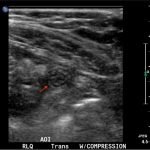

In the long axis video, the appendix appears as an enlarged, non-compressible, blind-ending tubular structure (white arrow) with distinct appendiceal wall layers and lack of peristalsis. In the short axis video, the appendix appears as a target sign (yellow arrow) between the abdominal and psoas muscles. The maximal outer diameter (MOD) measures 11.8mm and the appendix wall measures 0.17mm. There is trace adjacent free fluid and echogenic periappendiceal fat. Transverse axis video and image (red arrow) demonstrate that the appendix is not compressible. These findings are consistent with acute appendicitis.